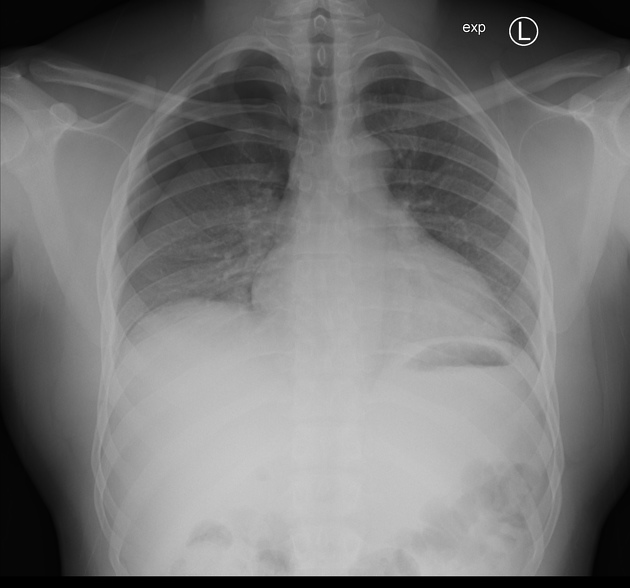

Describe the abnormality demonstrated.

Right-sided pneumothorax (loss of lung markings)